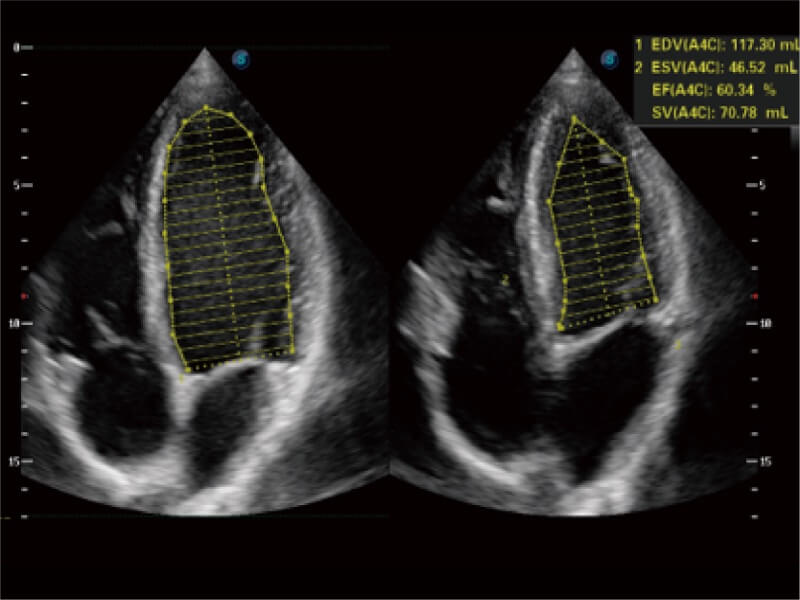

ProPet 80 配備了豐富的心臟探頭群、先進(jìn)的成像技術(shù)和專業(yè)的心臟測(cè)量工具,可幫助動(dòng)物醫(yī)生為不同體型和生理結(jié)構(gòu)的動(dòng)物提供心臟和心肌功能的全面評(píng)估。

能夠基于左心室壁追蹤和辛普森法,自動(dòng)計(jì)算射血分?jǐn)?shù),支持多個(gè)可移動(dòng)點(diǎn)描跡,與手動(dòng)測(cè)量相比,極大節(jié)省了動(dòng)物醫(yī)生的時(shí)間和精力。